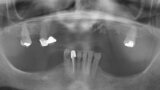

Fig. 12. Prótesis híbrida inmediata con 6 años de evolución y Rx Control a los 6 años.

Fig. 13. Prótesis híbrida inmediata con 6 años de evolución y Rx Control a los 6 años.